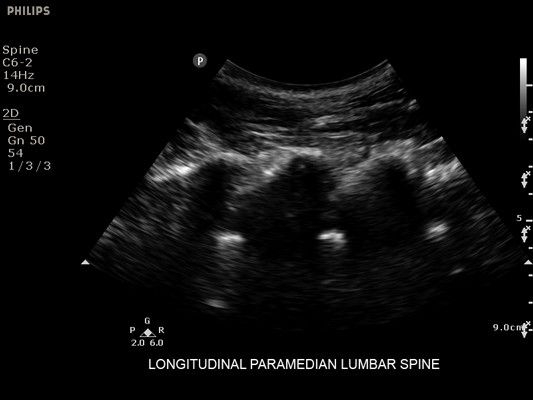

• Метки центральной линии на датчиках L12-4 и C6-2 для упрощения внеплоскостной навигации

• Исследования органов брюшной полости

• Конвексный УЗИ датчик Philips С6-2